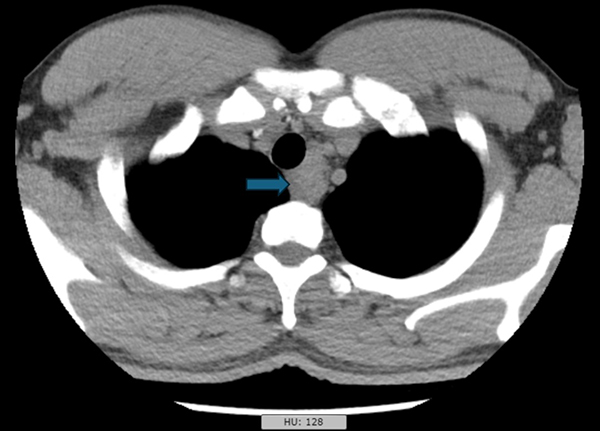

一个月前,我收到胸外科同事递来的一张内镜检查申请单:36岁男性,发现“纵隔肿物”。这类患者在我院并不少见,但每一次,我都如履薄冰。打开他的胸部CT,我仔细观察肿物与食管、气管的位置关系——距离够近,路径可行。我回复了一个字:“能。”——我们可以通过超声内镜穿刺活检,一探究竟。

胸部CT图片(纵隔肿物位于箭头所指位置)